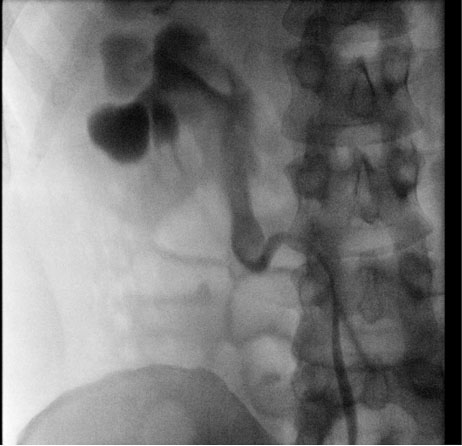

A 34-year-old male was referred for incidental right hydronephrosis observed on a CT abdomen and pelvis after a motor vehicle collision. The patient reported right flank pain following the accident. Past medical history and past surgical history were unremarkable. The patient denied hematuria, dysuria, lower urinary tract symptoms, or a history of urinary tract infections. Right costovertebral angle tenderness was present on physical examination. Urinalysis and urine culture were negative. Serum creatinine was 1.17 mg/dL, down from a previous measurement months before the motor vehicle accident of 1.77 mg/dL. A CT urogram revealed severe right hydronephrosis with possible ureteropelvic junction obstruction and diffuse thinning of the right renal parenchyma (Figure 1A and Figure 1B). A diuretic renogram was then obtained due to the thinning of the renal parenchyma and an unknown duration of hydronephrosis on the right kidney. There was a concern that the renal function may have declined over time due to prolonged obstruction. Subsequent diuretic nuclear renogram demonstrated normal uptake and a dilated right renal collecting system with delayed response to Lasix consistent with right partial high-grade obstruction (t1/2 25 minutes) (Figure 2). We then proceeded with cystoscopy with right retrograde pyelography to better detail the origin of the obstructive process. This demonstrated a tortuous proximal ureter with medial deviation and severe hydronephrosis consistent with a retrocaval ureter (Figure 3). The additional investigation using a retrograde pyelogram was performed for better diagnostic testing in case of future intraoperative planning for correction of the ureter. The retrograde pyelogram added details on the course of the proximal ureter and its’ anatomical tortuosity. A ureteral stent was placed for symptomatic relief of obstruction. The patient elected to undergo right robotic-assisted laparoscopic ureteroureterostomy. The patient was given prophylactic antibiotics. He was placed in the left lateral decubitus position with table flexion. Standard 8 mm da Vinci Xi (Intuitive Surgical, Sunnyvale, CA) trocar placement was performed for a right renal procedure (Figure 4). The robotic portion began with medial reflection the hepatic flexure and exposure of the right renal pelvis in standard fashion. The renal pelvis was expectedly dilated and prominent. The proximal ureter and IVC were identified. The ureteropelvic junction was dissected and encircled with a vessel loop. The ureter was found to be coursing posterior to the IVC, confirming retrocaval ureter. Identification of the ureter distal to the level of obstruction on the medial side of the IVC in the interaortocaval space was conducted (Figure 5). The distal aspect of the ureter was isolated with a second vessel loop. Care was taken not to unduly devascularize the ureter while mobilizing it to the extent allowing for transection and transposition of the ureter ventral to the IVC. The proximal ureter was sharply transected just distal to the ureteropelvic junction. The previously placed ureteral stent was removed. The ureter was transposed anterior to the IVC without tension (Figure 6). The proximal and distal ends of the ureter were spatulated, and a standard ureteroureterostomy was performed with two running stitches of 4-0 PDS suture (Ethicon, Bridgewater, NJ). Prior to completion of the ureteral anastomosis, a new 6 French, 28 cm double-J ureteral stent was then advanced antegrade over a Sensor wire (Boston Scientific, Marlborough, MA). The proximal stent coil was placed into the renal pelvis, and the anastomosis was completed. A JP drain was placed, and a Foley catheter was kept indwelling.

Figure 3: Cystoscopy with right retrograde pyelography showing ureteropelvic junction obstruction and a tortuous proximal ureter.

Share Image:

Retrocaval ureter is classified into two types. Type 1 is more common, accounting for 90% of cases, and is characterized by more distal obstruction behind the IVC at the L3–L4 level [2],[3]. This type resembles a J- or S-shape and can be associated with moderate to severe hydronephrosis [2]. Type 2 represents the remaining 10% of retrocaval ureters and causes mild or no hydronephrosis with obstruction occurring near the level of the renal pelvis [2],[3]. The patient in the present report is deemed to have had a type 1 retrocaval ureter. Imaging is fundamental in the diagnosis of retrocaval ureter, which also serves as a roadmap for surgical correction. Though renal ultrasound may be a first step as it readily identifies hydronephrosis, often it cannot differentiate the source of any distal obstruction. Historically, intravenous pyelography was used to diagnose retrocaval ureter [4],[5]. However, modern cross-sectional imaging such as CT urography provides greater anatomical detail for surgical planning purposes. Retrograde pyelography remains a useful adjunct in cases where CT urography does not sufficiently image the course of the ureter. In this case, the CT urogram failed to detail the course of the ureter posterior to the IVC. On the CT urogram findings, there was severe right hydronephrosis with possible ureteropelvic junction obstruction. The addition of the retrograde pyelogram showed the tortuous proximal ureter with medial deviation and severe hydronephrosis consistent with a retrocaval ureter. Based on the CT urogram findings alone this diagnosis would have been difficult to obtain. The additional of a retrograde pyelogram should be considered when surgeons are concerned for this rare anatomical abnormality. Our patient underwent a robotic ureteroureterostomy for surgical correction of a retrocaval leading to hydronephrosis and flank pain. He was doing well postoperatively and his symptoms improved. The surgical steps of the robotic procedure were detailed, adding a reference and review for surgeons regarding this rare disease process.